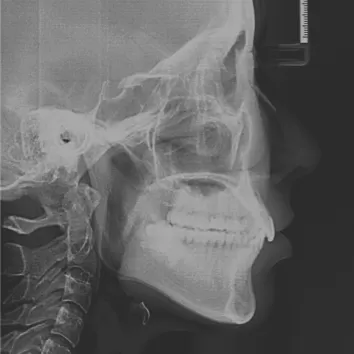

Rayons X avant le traitement

[Radiographie panoramique/Céphalogramme latéral]